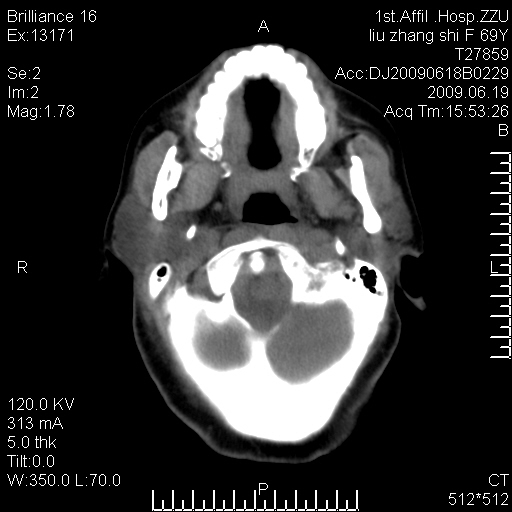

标题: CT26782:女,69岁,颈部占位,3天后公布病理结果。

【病理证实系列】女,69岁,颈部占位,有病理结果,3天后公布。(由于病例时间较久,临床资料不全,请网友见谅)本系列将有几百种常见、少见及罕见病例,均经病理证实。病例资料来自郑州大学第一附属医院。与网友共享,本人有空就发。

病理结果:颈部非霍奇金淋巴瘤。